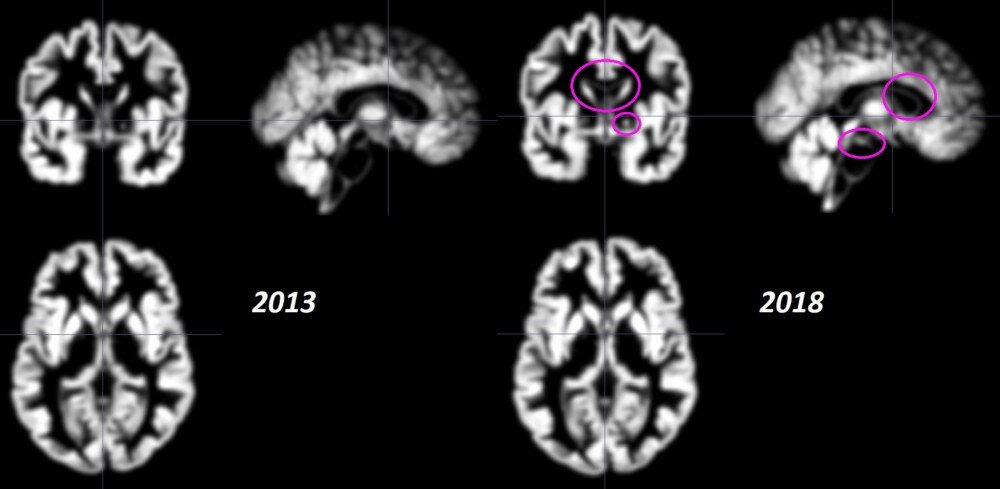

Изображения мозга ниже - это сканированные изображения головного мозга Брайана. Тот, что слева, был заснят в рамках исследования в 2013 году, когда Пенни только бросил наркотики после 15 лет зависимости. Снимок справа был сделан в мае 2018 года в рамках документального фильма о стрессе.

Снимки мозга, сделанные в 2013 и 2018 годах. Фотографии содержат срез, показывающий переднюю спайку, стандартную анатомическую структуру, используемую для сравнения снимков головного мозга.

Это означает, что за 5 лет между сканированиями возраст мозга Брайана уменьшился более чем на 6 лет. Трудно визуально определить различия в плотности серого вещества, но если вы присмотритесь, вы можете увидеть конкретные различия в фиолетовых кругах ниже. Сканы справа также выглядят ярче со всех сторон.

Сканирование серого вещества мозга, сделанное в 2013 и 2018 годах. Несмотря на то, что оно незаметно, на сканировании 2018 года наблюдается большая плотность серого вещества. В отличие от сравнительных сканирований выше, эти сканы были обработаны с использованием специальной техники, которая требуется для анализа.